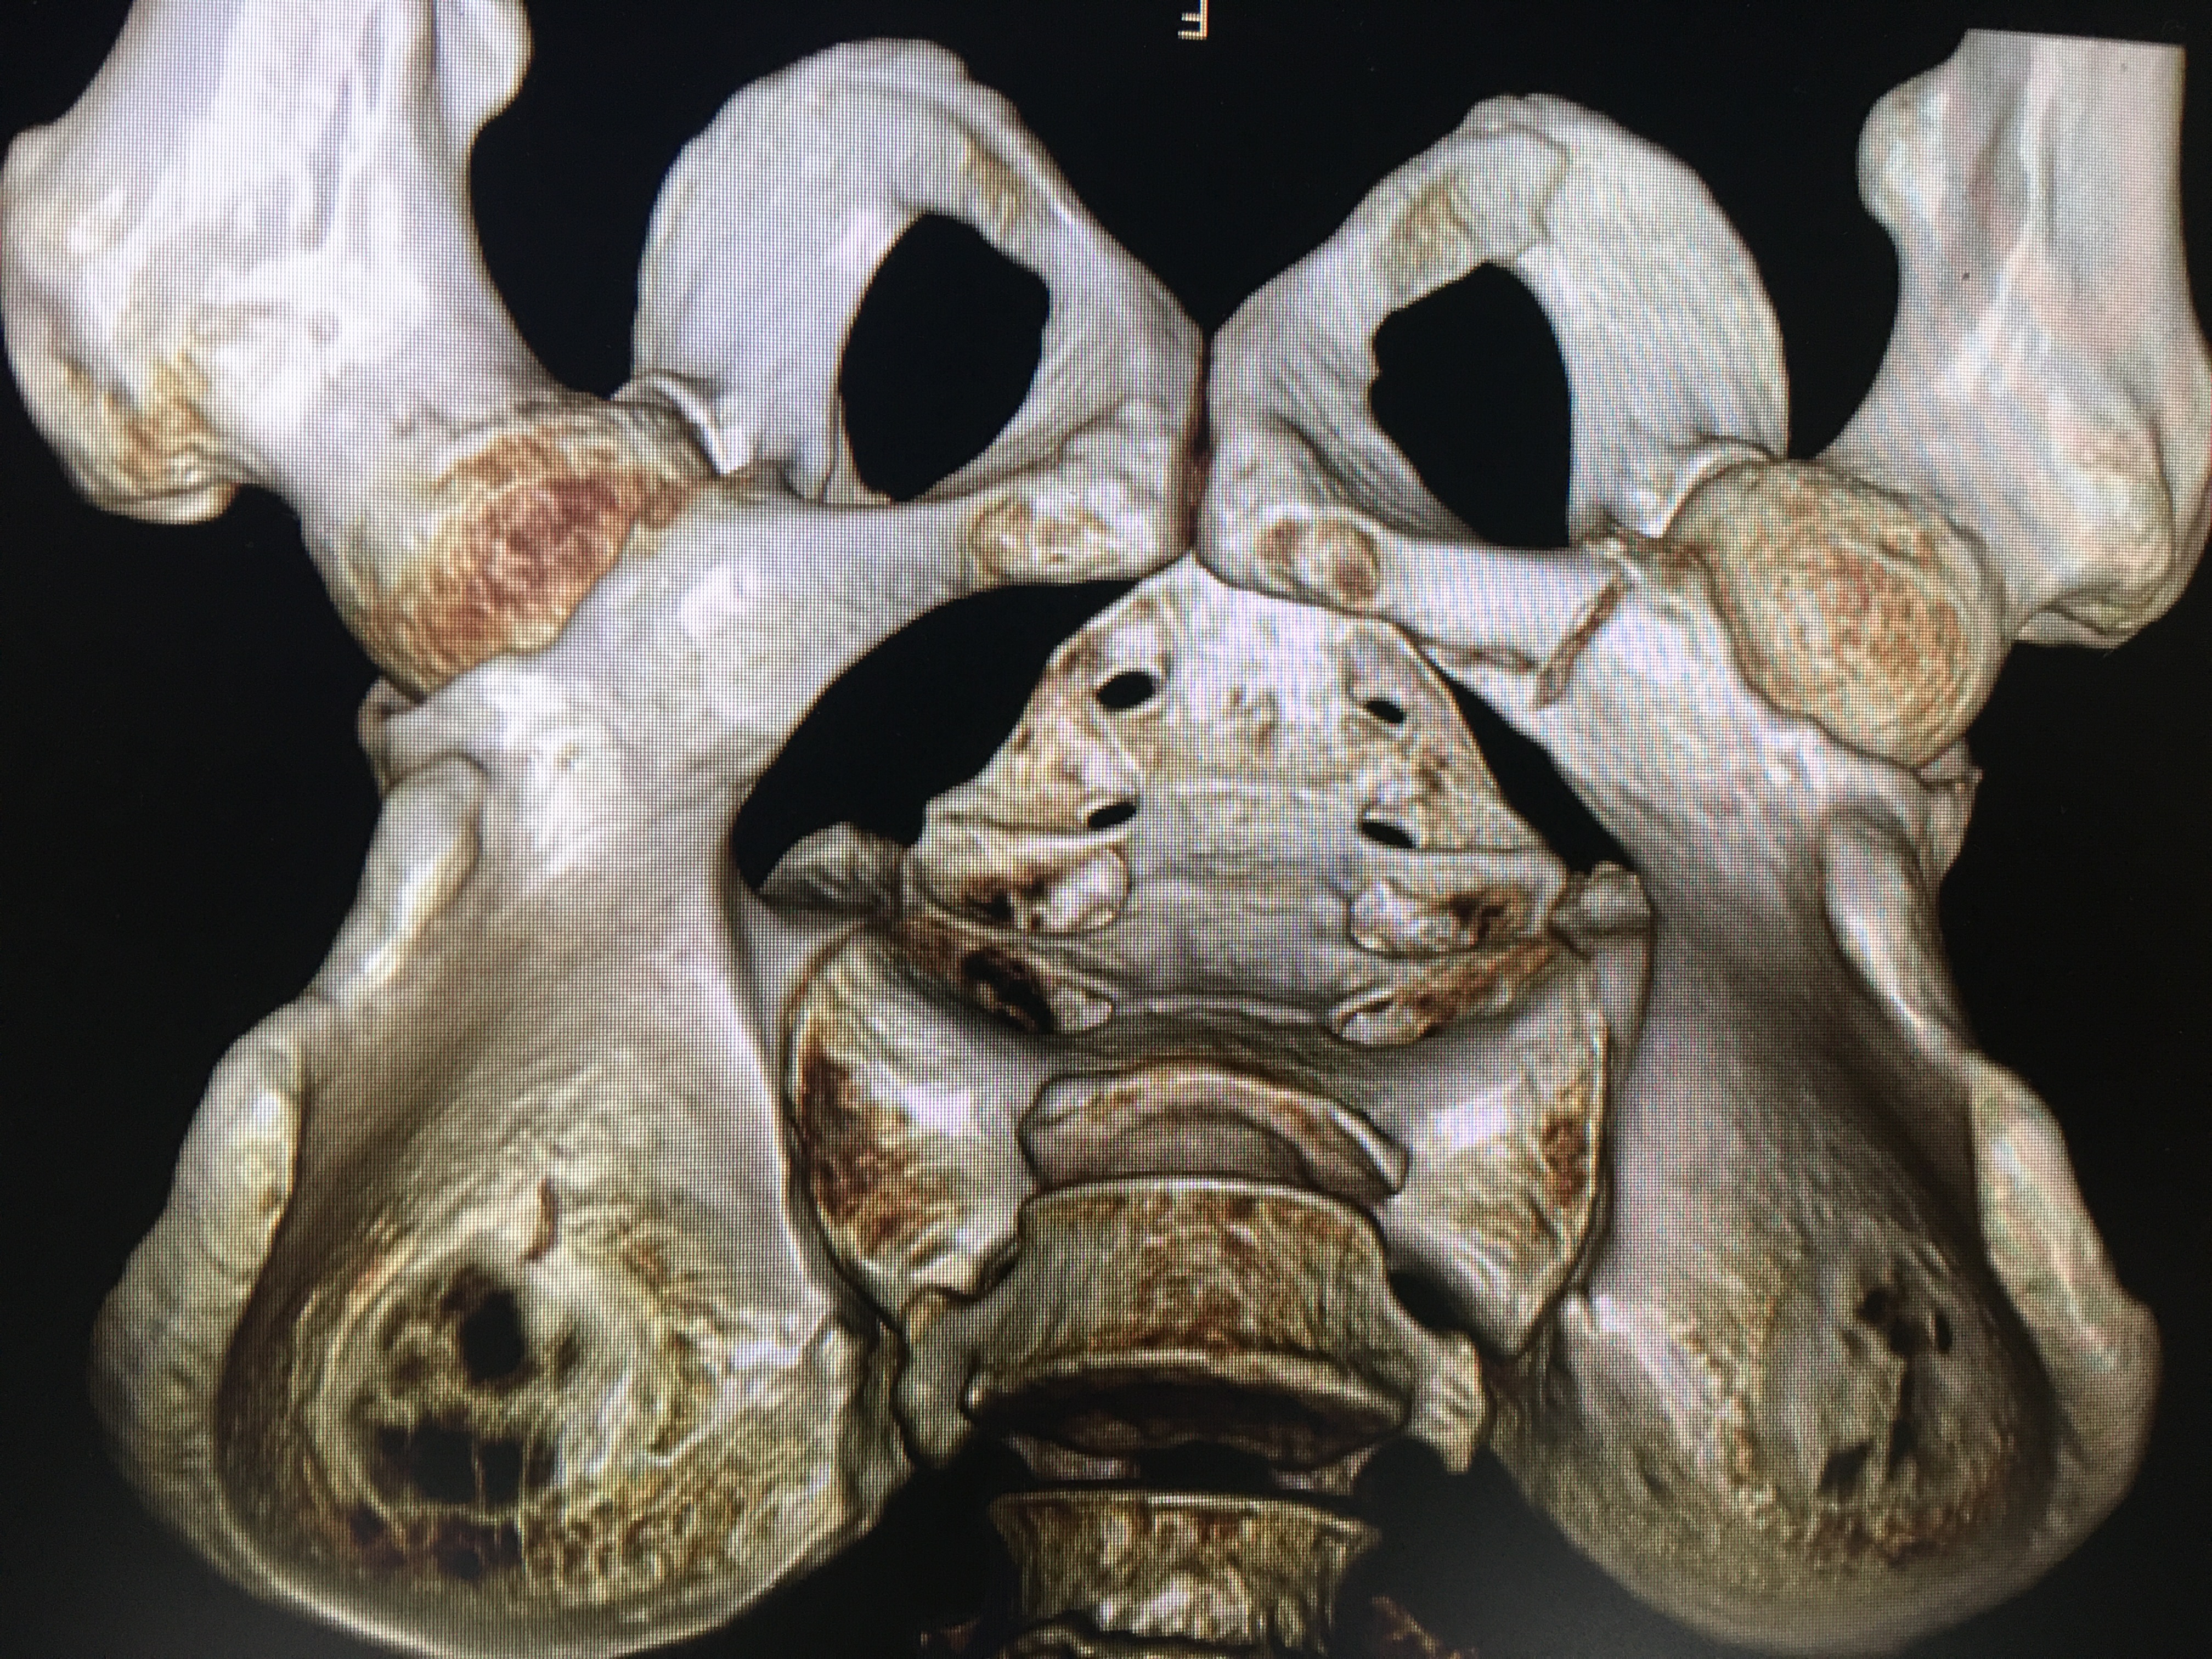

三维图形更直观